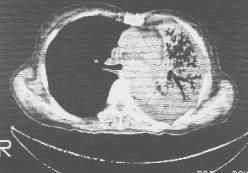

阻塞性肺不張的X線表現與阻塞的部位和不張的肺內有無已經存在的病變或並發感染有關。阻塞可以在主支氣管、葉或段支氣管、細支氣管,而導致一側性、肺葉、肺段和小葉的肺不張。肺不張的範圍不同,其X線表現也不同。

(2)肺葉不張:不同肺葉不張的X線表現不同,但其共同特點是肺葉縮小,密度均勻增高,葉間裂呈向心性移位。縱隔及肺門可有不同程度的向患部移位。鄰近肺葉可出現代償性肺氣腫。

(4)小葉性不張:小葉性不張(lobularatelectasis)多見於支氣管哮喘及支氣管肺炎,由於多數末梢細支氣管被粘液阻塞所致。X線表現為多數小斑片狀影,其周圍可有透明的氣腫帶。